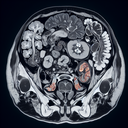

МРТ органів малого тазу

Магнітно-резонансна томографія (МРТ) органів малого тазу — це неінвазивний метод діагностики, що використовує магнітні поля та радіохвилі для отримання детальних зображень внутрішніх структур. Цей метод дозволяє лікарям оцінити стан органів малого тазу, таких як сечовий міхур, простата у чоловіків, матка та яєчники у жінок, а також навколишні тканини й лімфатичні вузли. ### Переваги МРТ малого тазу: - **Високий рівень деталізації:** Дозволяє виявити зміни в тканинах, які можуть бути непомітні при інших методах діагностики...